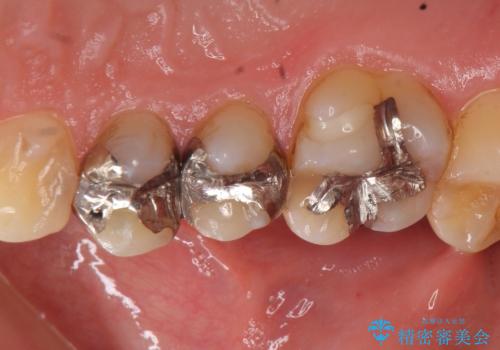

- 右上の銀歯を白くしたいといらっしゃった方の症例です。

右上4、5番目の歯はオールセラミッククラウンによる補綴、6番目の歯はセラミックインレーによる修復を行いました。